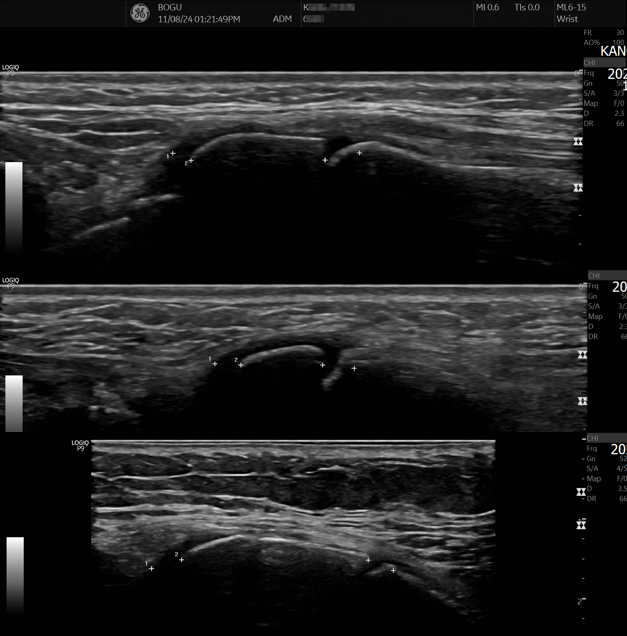

만성 피로 환자 치료케이스-대사증후군 만성염증 환자의 증상(2)-다발성 관절통과

생기능의학 한의계는 어떻게 활용하면 좋을까(61)스테로이드나 면역억제제 등으로 치료되지 않는 환자의 진료는 우선 체질을 판단해야 한다. 체질을 판단할 때는 근육과 지방으로 판단하며 근육이 잘 생성되는 체질과 잘 생성되지 않는 체질, 그리고 지방이 많고 적은 체질로 나누면 근육이